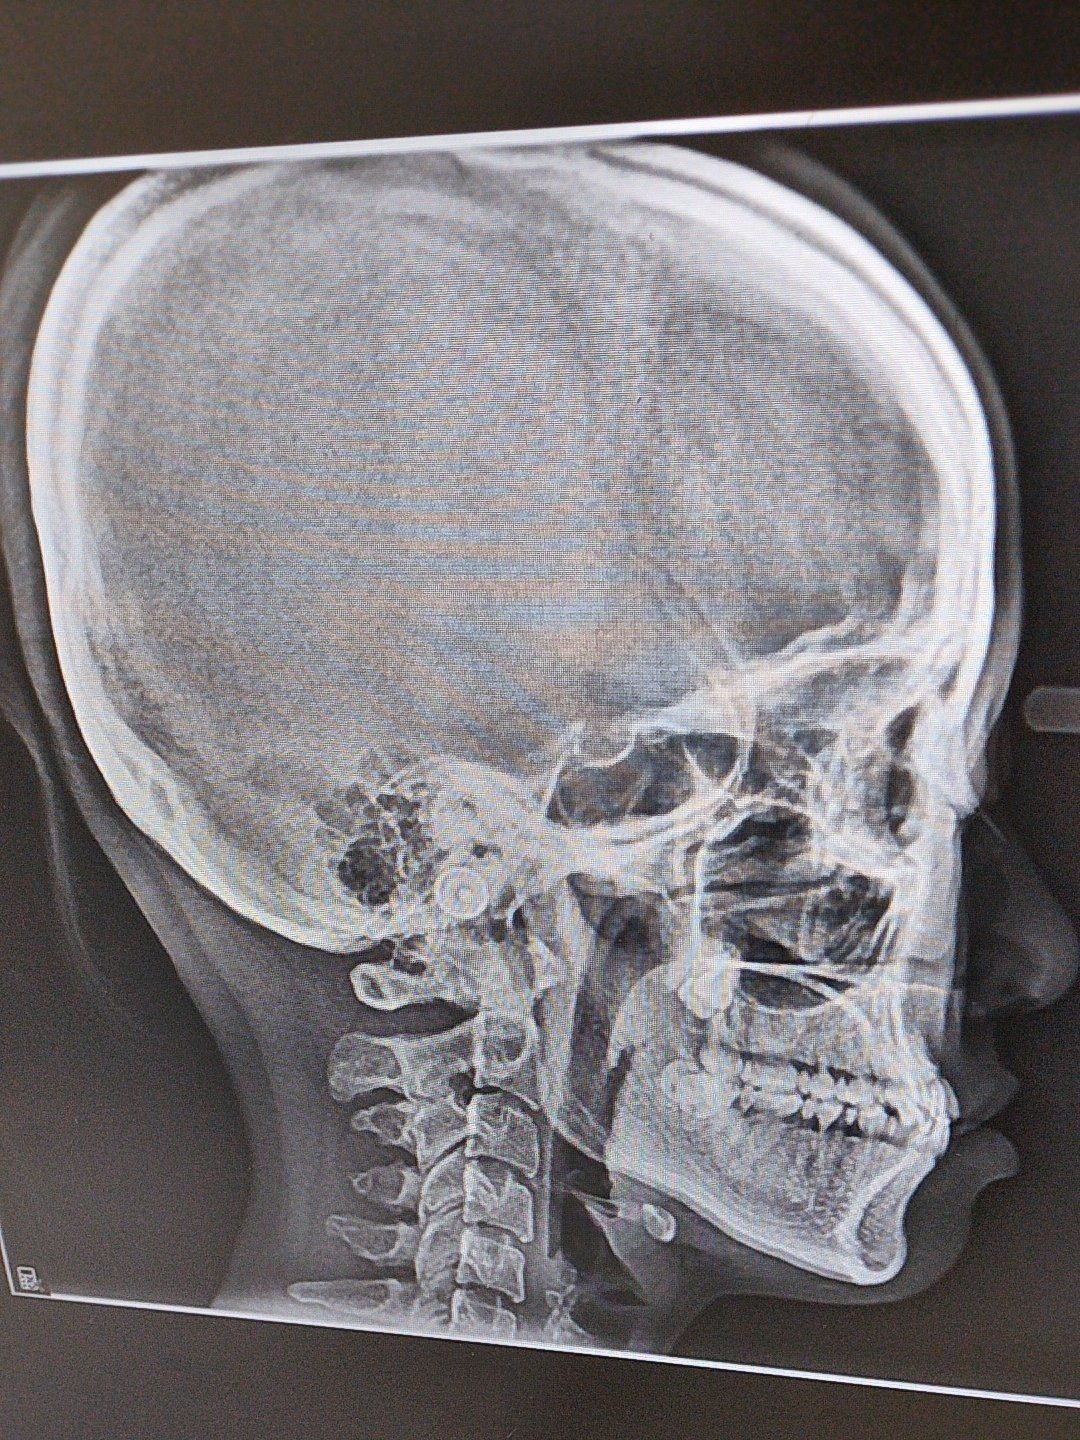

偏颌x光片

地包天➕偏颌

偏颌反颌无法和解